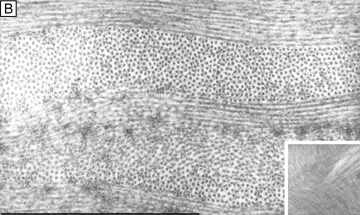

The anterior surface of the human cornea is covered by a transparent, nonkeratinized, stratified (five- to seven-cell layer) squamous epithelium uniformly around 50 μm in thickness that is continuous with the epithelium of the limbus and conjunctiva (Figs. 1, 2, and 3). The basal corneal epithelial cells actively secrete extracellular material (type IV collagen, laminin, heparin, and small amounts of fibronectin and fibrin) that forms an underlying 75-nm thick basement membrane called the basal lamina. On electron microscopy, the morphology of basal lamina appears to be composed of two distinct layers: a 25-nm thick lamina lucida and a 50 nm thick lamina densa (Fig. 3).

Fig. 3. Transmission electron micrograph (3,500×) of the central corneal epithelium with a summary diagram (inset). Microvilli project from the anterior corneal surface into the tear film. S, squamous cells; W, wing cells; B, basal epithelial cells. Bar = 1 μm. (Inset modified from Hogan MJ, et al. Histology of the human eye. Philadelphia, WB Saunders, 1971.)

The epithelial cells differentiate from the basal layer to form two to three cell layers of wing cells and finally to form two to three cell layers of squamous cells (Fig. 3). The squamous cells form a barrier junction because they are surrounded by a continuous encircling band of zonula occludens tight junctions, which serve as a semipermeable, high-resistance (12–16 kΩ cm2) membrane6,7 by closing off the intercellular space. This barrier prevents the movement of fluid from the tears into the stroma and also protects the cornea and intraocular structures from infectious pathogens. The apical surface of the corneal epithelium is specialized to maintain the tear film as microplicae and microvilli on the surface of the most superficial epithelial cells is covered with a glycocalyx and membrane-spanning mucins (MUC 1 and possibly MUC 4); altogether these structures and substances form the 1.0 μm thick mucinous layer of the tear film (Fig. 5).8–10